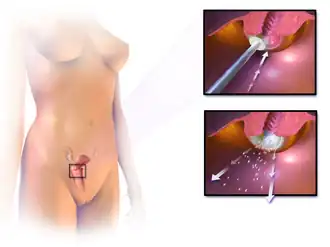

A radical trachelectomy can be performed abdominally[108] or vaginally[109] and opinions are conflicting as to which is better.[110] A radical abdominal trachelectomy with lymphadenectomy usually only requires a two- to three-day hospital stay, and most women recover very quickly (about six weeks). Complications are uncommon, although women who can conceive after surgery are susceptible to preterm labour and possible late miscarriage.[111] A wait of at least one year is generally recommended before attempting to become pregnant after surgery.[112] Recurrence in the residual cervix is rare if the trachelectomy has cleared the cancer.[107] Yet, women are recommended to practice vigilant prevention and follow-up care, including Pap screenings/colposcopy, with biopsies of the remaining lower uterine segment as needed (every 3–4 months for at least 5 years) to monitor for any recurrence in addition to minimizing any new exposures to HPV through safe sex practices until one is actively trying to conceive.

Early stages (IB1 and IIA less than 4 cm) can be treated with radical hysterectomy with removal of the lymph nodes or radiation therapy. Radiation therapy is given as external beam radiotherapy to the pelvis and brachytherapy (internal radiation). Women treated with surgery who have high-risk features found on pathologic examination are given radiation therapy with or without chemotherapy to reduce the risk of relapse. A Cochrane review has found moderate-certainty evidence that radiation decreases the risk of disease progression in people with stage IB cervical cancer when compared to no further treatment.[113] However, little evidence was found on its effects on overall survival.[113]